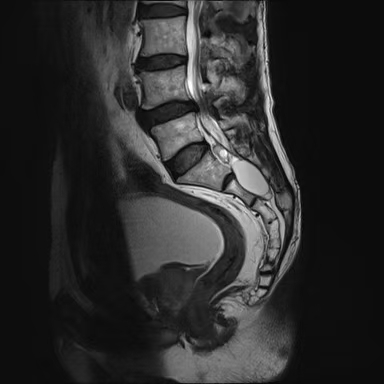

3. MRI檢查:是診斷椎管內(nèi)脊膜囊腫最可靠的檢查方法,囊腫呈長條狀囊袋形、卵圓形和不規(guī)則形等,囊液信號與腦脊液信號相似,TlWI呈低信號,T2WI呈高信號。IB型位于骶管內(nèi),與硬脊膜囊之間有脂肪相隔。Ⅱ型位于硬脊膜囊側(cè)方,囊內(nèi)有神經(jīng)根存在。